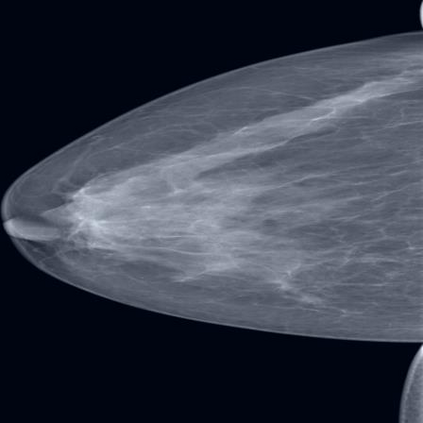

The assessment of breast density is crucial in the context of breast cancer screening, especially in populations with a higher percentage of dense breast tissues. This study introduces a novel data augmentation technique termed Attention-Guided Erasing (AGE), devised to enhance the downstream classification of four distinct breast density categories in mammography following the BI-RADS recommendation in the Vietnamese cohort. The proposed method integrates supplementary information during transfer learning, utilizing visual attention maps derived from a vision transformer backbone trained using the self-supervised DINO method. These maps are utilized to erase background regions in the mammogram images, unveiling only the potential areas of dense breast tissues to the network. Through the incorporation of AGE during transfer learning with varying random probabilities, we consistently surpass classification performance compared to scenarios without AGE and the traditional random erasing transformation. We validate our methodology using the publicly available VinDr-Mammo dataset. Specifically, we attain a mean F1-score of 0.5910, outperforming values of 0.5594 and 0.5691 corresponding to scenarios without AGE and with random erasing (RE), respectively. This superiority is further substantiated by t-tests, revealing a p-value of p<0.0001, underscoring the statistical significance of our approach.